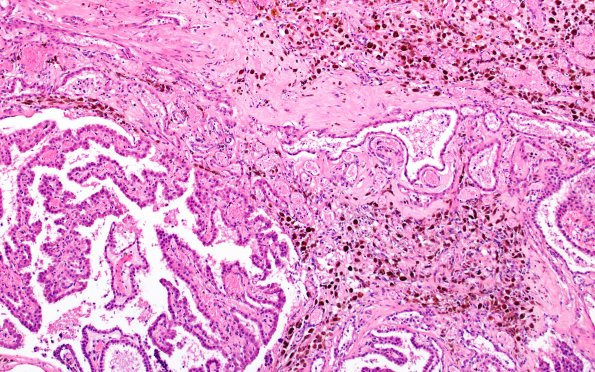

Washington University Experience | VASCULAR | Hemorrhage - Neonatal | 29B5 IVH (Case 29) N11 H&E 10X 3

The choroid plexus shows admixed hemorrhage, hemosiderin deposition, fibrosis and residual non-vascularized choroid plexus. (H&E)